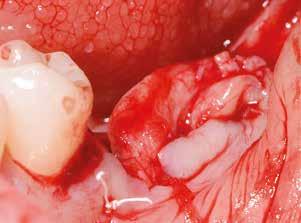

Sebészi technika

Helyi érzéstelenítést végeztünk a műtéti területen artikain és 1:100 000 adrenalin segítségével. A recipiens területet előkészítettük, élesen disszekciót végeztünk, hogy egy izomtapadástól mentes periosteum ágyat képezhessünk. Ettől disztálisan két párhuzamos parakresztális metszést végeztünk egy 15C-s szikepengével, majd a metszéseket egy

2–5. ábra: A metszések és a deepitelizáció. – 6–9. ábra: Félvastag lebeny. – 10. ábra: A nyelezett ínylebeny „bepróbálása”.

horizontális metszéssel kötöttük össze (2–5. ábra). A metszések hosszát és a köztük lévő távolságot minden esetben a lágyszövet augmentációhoz szükséges keratinizált szövet határozza meg. A lebeny deepitelizációját egy 15C-s szikepengével végeztük (6. ábra). Ezt követően félvastag lebenyt preparáltunk (7. ábra). A lebenyt apikálisan, az alapjáról belső, felületes metszéssel felszabadítottuk, hogy passzívan áthelyezhessük és rögzíthessük, feszülés nélkül. Meziális irányba 180 fokkal átforgattuk (8–9. ábra). A meziális papillát alagúttechnikával (tunnelling technique) készítettük elő a graft befogadására (10. ábra). Az így kialakított lebenyt a recipiens ágyban rögzítettük az újonnan kialakított vesztibulum alapjánál 5-0 nem felszívódó PTFE (Coreflon, IMPLACORE) varratokkal. A graftot behajtottuk az ínyszél alá és meziális oldalon rögzítettük PTFE varratokkal (11–14. ábra)

A műtétet követően napi kétszeri, 0,12%-os klórhexidin tartalmú szájvízzel történő öblögetést javasoltunk a páciensnek, két héten keresztül. Gyulladáscsökkentésre 8 óránként 400 mg Ibuprofént javasoltunk, három napon keresztül. A páciens elmondása szerint sem fájdalmat, sem különösebb diszkomfortot nem tapasztalt. Ezt követően, további 4 héten keresztül, 0,2%-os klórhexidin tartalmú szájvízzel történő öblögetést javasoltunk a betegnek és instruáltuk, hogy lehetőleg ne mossa fogkefével az érintett területet. A varratokat egy héttel később távolítottuk el. A donor és a recipiens terület – 10 nappal a műtétet követően – kiválóan gyógyult (15–16. ábra). Az ezt követő kontrollokat a következő időpontokban ejtettük meg: kettő, illetve négy héttel a műtét után, majd három, hat és tizenkét hónappal később, ezt követően pedig félévente (17–20. ábra). Minden kontroll alkalmával professzionális fenntartó kezelést végeztünk a területen.

11. ábra: A Kígyó lebeny (varratok disztális részén).

12. ábra: A graftot a meziális oldalon rögzítettük PTFE varrattal.

13. ábra: A graft az ínyszél alá húzva.

14. ábra: Közvetlenül a műtét utáni kép, az utolsó öltések lenyomják a lebenyt, hogy ne maradjon szabad terület.

15. ábra: Tíz nappal a műtét után készült kép, kiválóan gyógyult mind a donor, mind a recipiens terület.